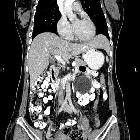

Newborn with

palpable lower abdominal massAxial CT with contrast of the abdomen shows a large simple cystic mass in the left side of the abdomen.The diagnosis was mesenteric cyst.